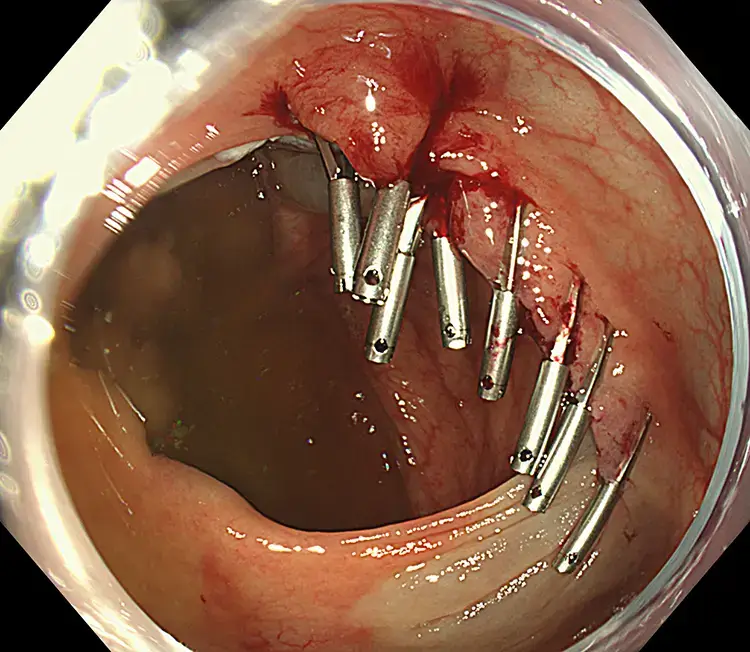

This is a large, 6cm ascending colon tumour which was successfully resected by EMR.

Endoscopic Mucosal Resection (EMR) is performed during colonoscopy. Fluid is gently injected beneath the polyp to lift it away from the bowel wall. A fine wire loop (snare) is then placed around the polyp and removed with a small electric current, which also seals blood vessels to reduce bleeding. Larger polyps may be removed in pieces. All removed tissue is collected and sent to the laboratory for analysis.